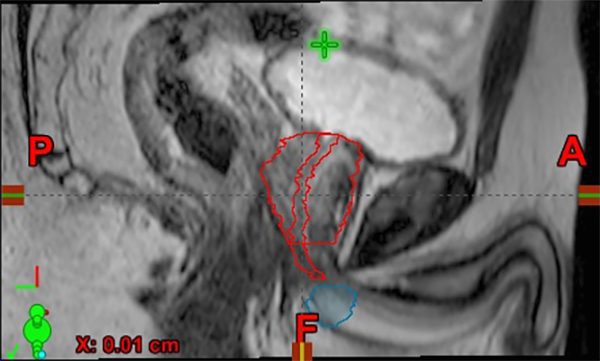

Side view of MRI of the prostate showing the urethra (long structure in red) and penile bulb (round structure in blue)